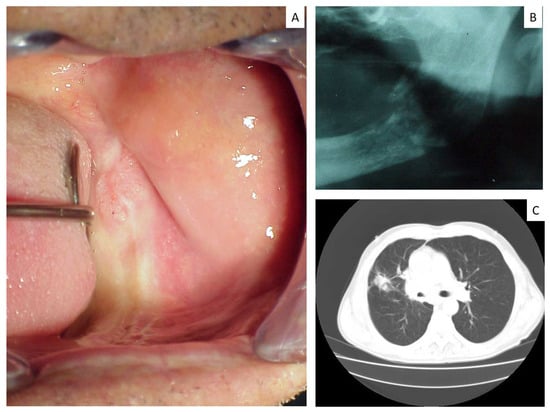

| Case | Age | Sex | Site/Sites | Primary Lung Tumor | Other Sites | First Sign of Disease |

|---|---|---|---|---|---|---|

| 5 | 57 | M | Mandible | Non small cell carcinoma | n.a. | No |

| 14 | 80 | M | Mandible | Squamous carcinoma | Vertebra | No |